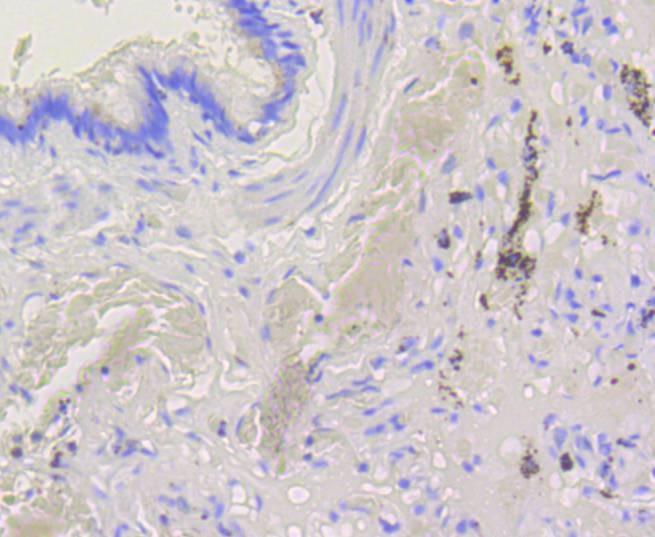

2. Immunohistochemical analysis of paraffin-embedded human lung tissue using anti-Bak antibody. Counter stained with hematoxylin.

3. Immunohistochemical analysis of paraffin-embedded mouse lung tissue using anti-Bak antibody. Counter stained with hematoxylin.